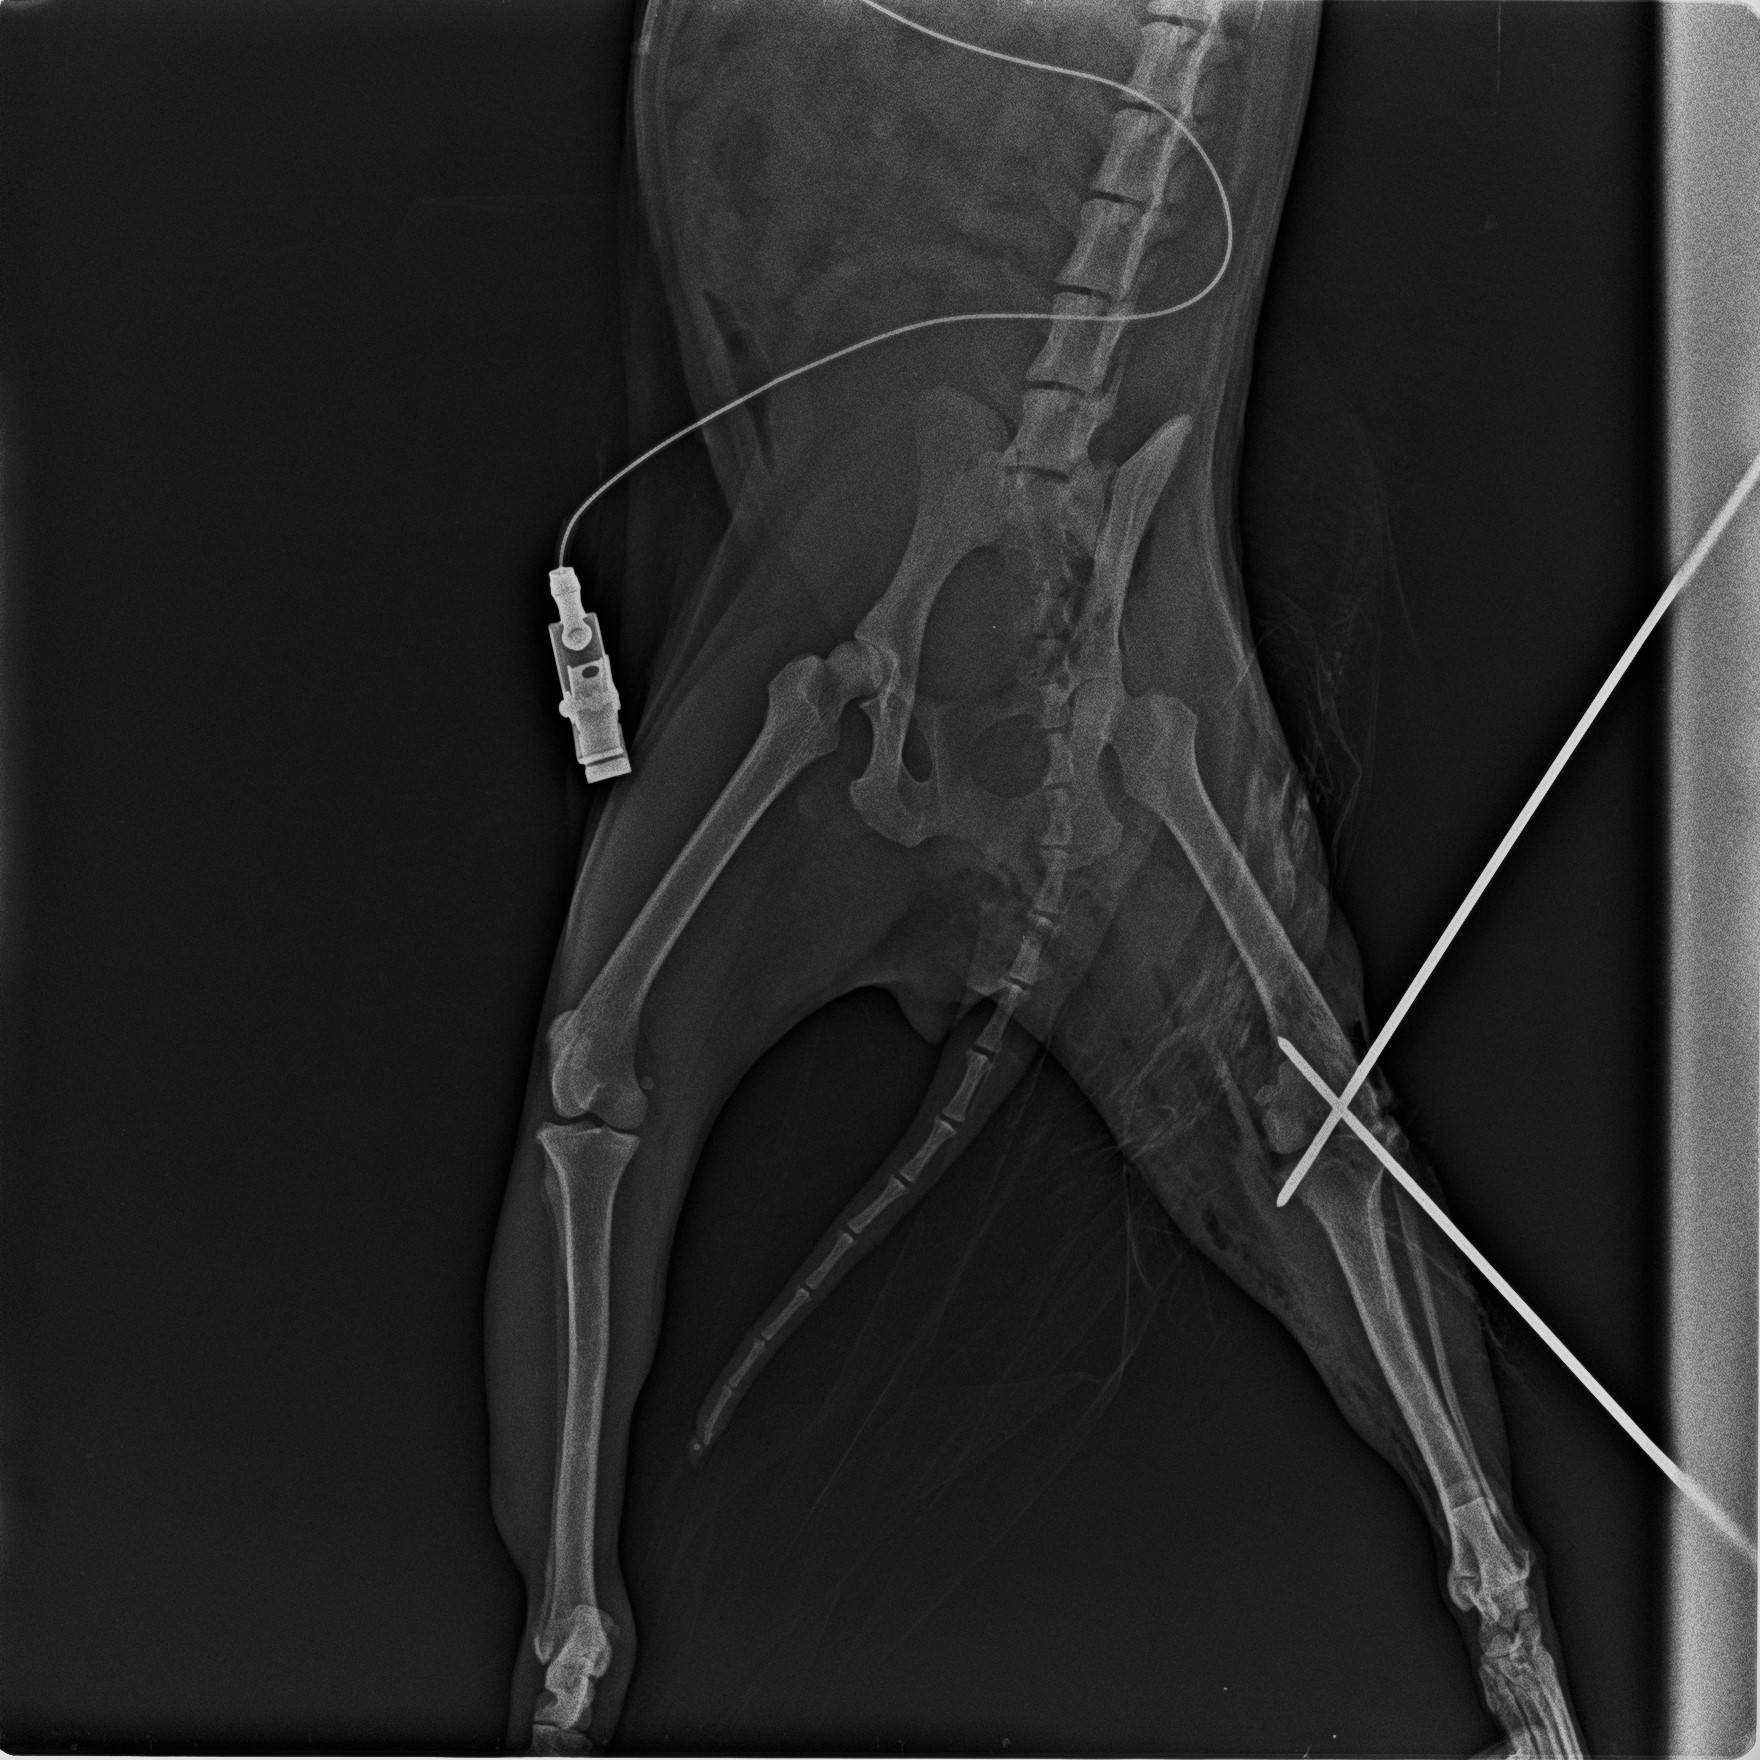

その苦労の結果がコチラ。

一応クロスにピンを打ち込み、固定することができました。

手術が終わったら、患肢を動かさないようテーピングを行いました。